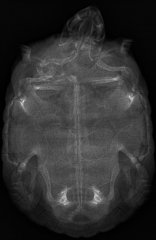

Pelomedusa subrufa